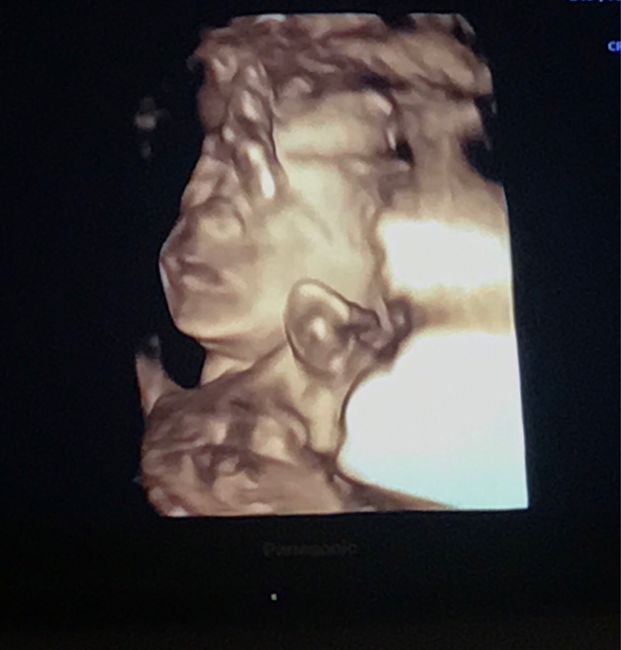

Future Mamme Febbraio 2021

Da Federica , Il 13 Ottobre 2020 alle 20:57

Buongiorno future mamme! Oggi ho scoperto il mio positivo e secondo l’app la DPP è 04/02/2021. Sono già mamma di Giorgia, 1 anno, e non vedevamo l’ora di darle un...